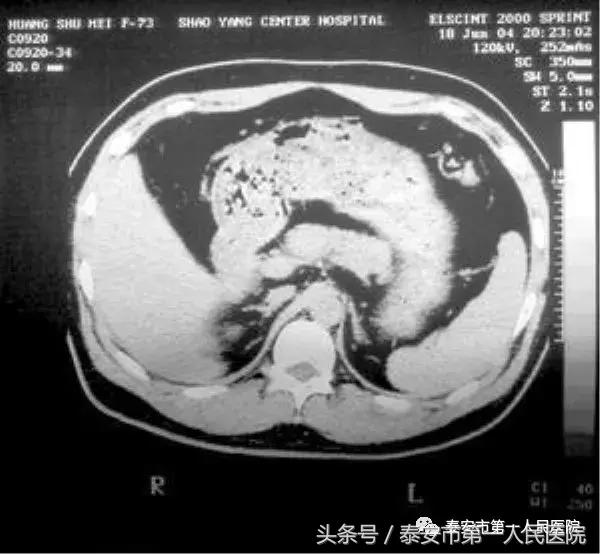

入院后完善检查,上腹部CT示胰腺炎。腹腔积液、双肺炎症、双侧胸腔积液、心包积液,床边心电图示T波改变,血常规示白细胞 13.85×109,血淀粉酶 873U/L,生化示钾离子6.9 mmol/L,钠离子125mmol/L,氯离子80.0mmol/L,钙离子1.6mmol/L,肝功能受损,葡萄糖 32.4mmol/L,甘油三酯29.93mmol/L,尿素氮11.6mmol/L,肌酐200ummol/L,肌酸激酶同功酶轻度升高,乳酸脱氢酶 743u/L,超敏C反应蛋白明显升高,患者自发病后至入院后尿量约300ml,为浓茶样。

诊断为急性化脓性胰腺炎(重症) 胆囊炎、上消化道出血、腹腔积液、胸腔积液、心包积液、急性肾功能衰竭、心肌损害、糖尿病、高脂血症、电解质紊乱。患者心率为105-130次/分,给予下达病重通知,持续胃肠减压,抑制胰腺分泌,抑酸,抗炎治疗,给予持续导尿,记出入量,给予胰岛素48u加入生理盐水48ml持续泵入,给予碳酸氢钠125ml静滴,持续心电监护,持续低流量吸氧,补充氯化钠,监测电解质、肝肾功、心功、血糖等。

(十五)CT。CT检查是诊断重症急性胰腺炎的重要手段,准确率可达70%~80%,可显示胰腺和胰腺后的图像。重症急性胰腺炎可见肾周围区消失、网膜囊和网膜脂肪变性、密度增厚、胸腔积液、腹水等病变。 (普外二科 高健)